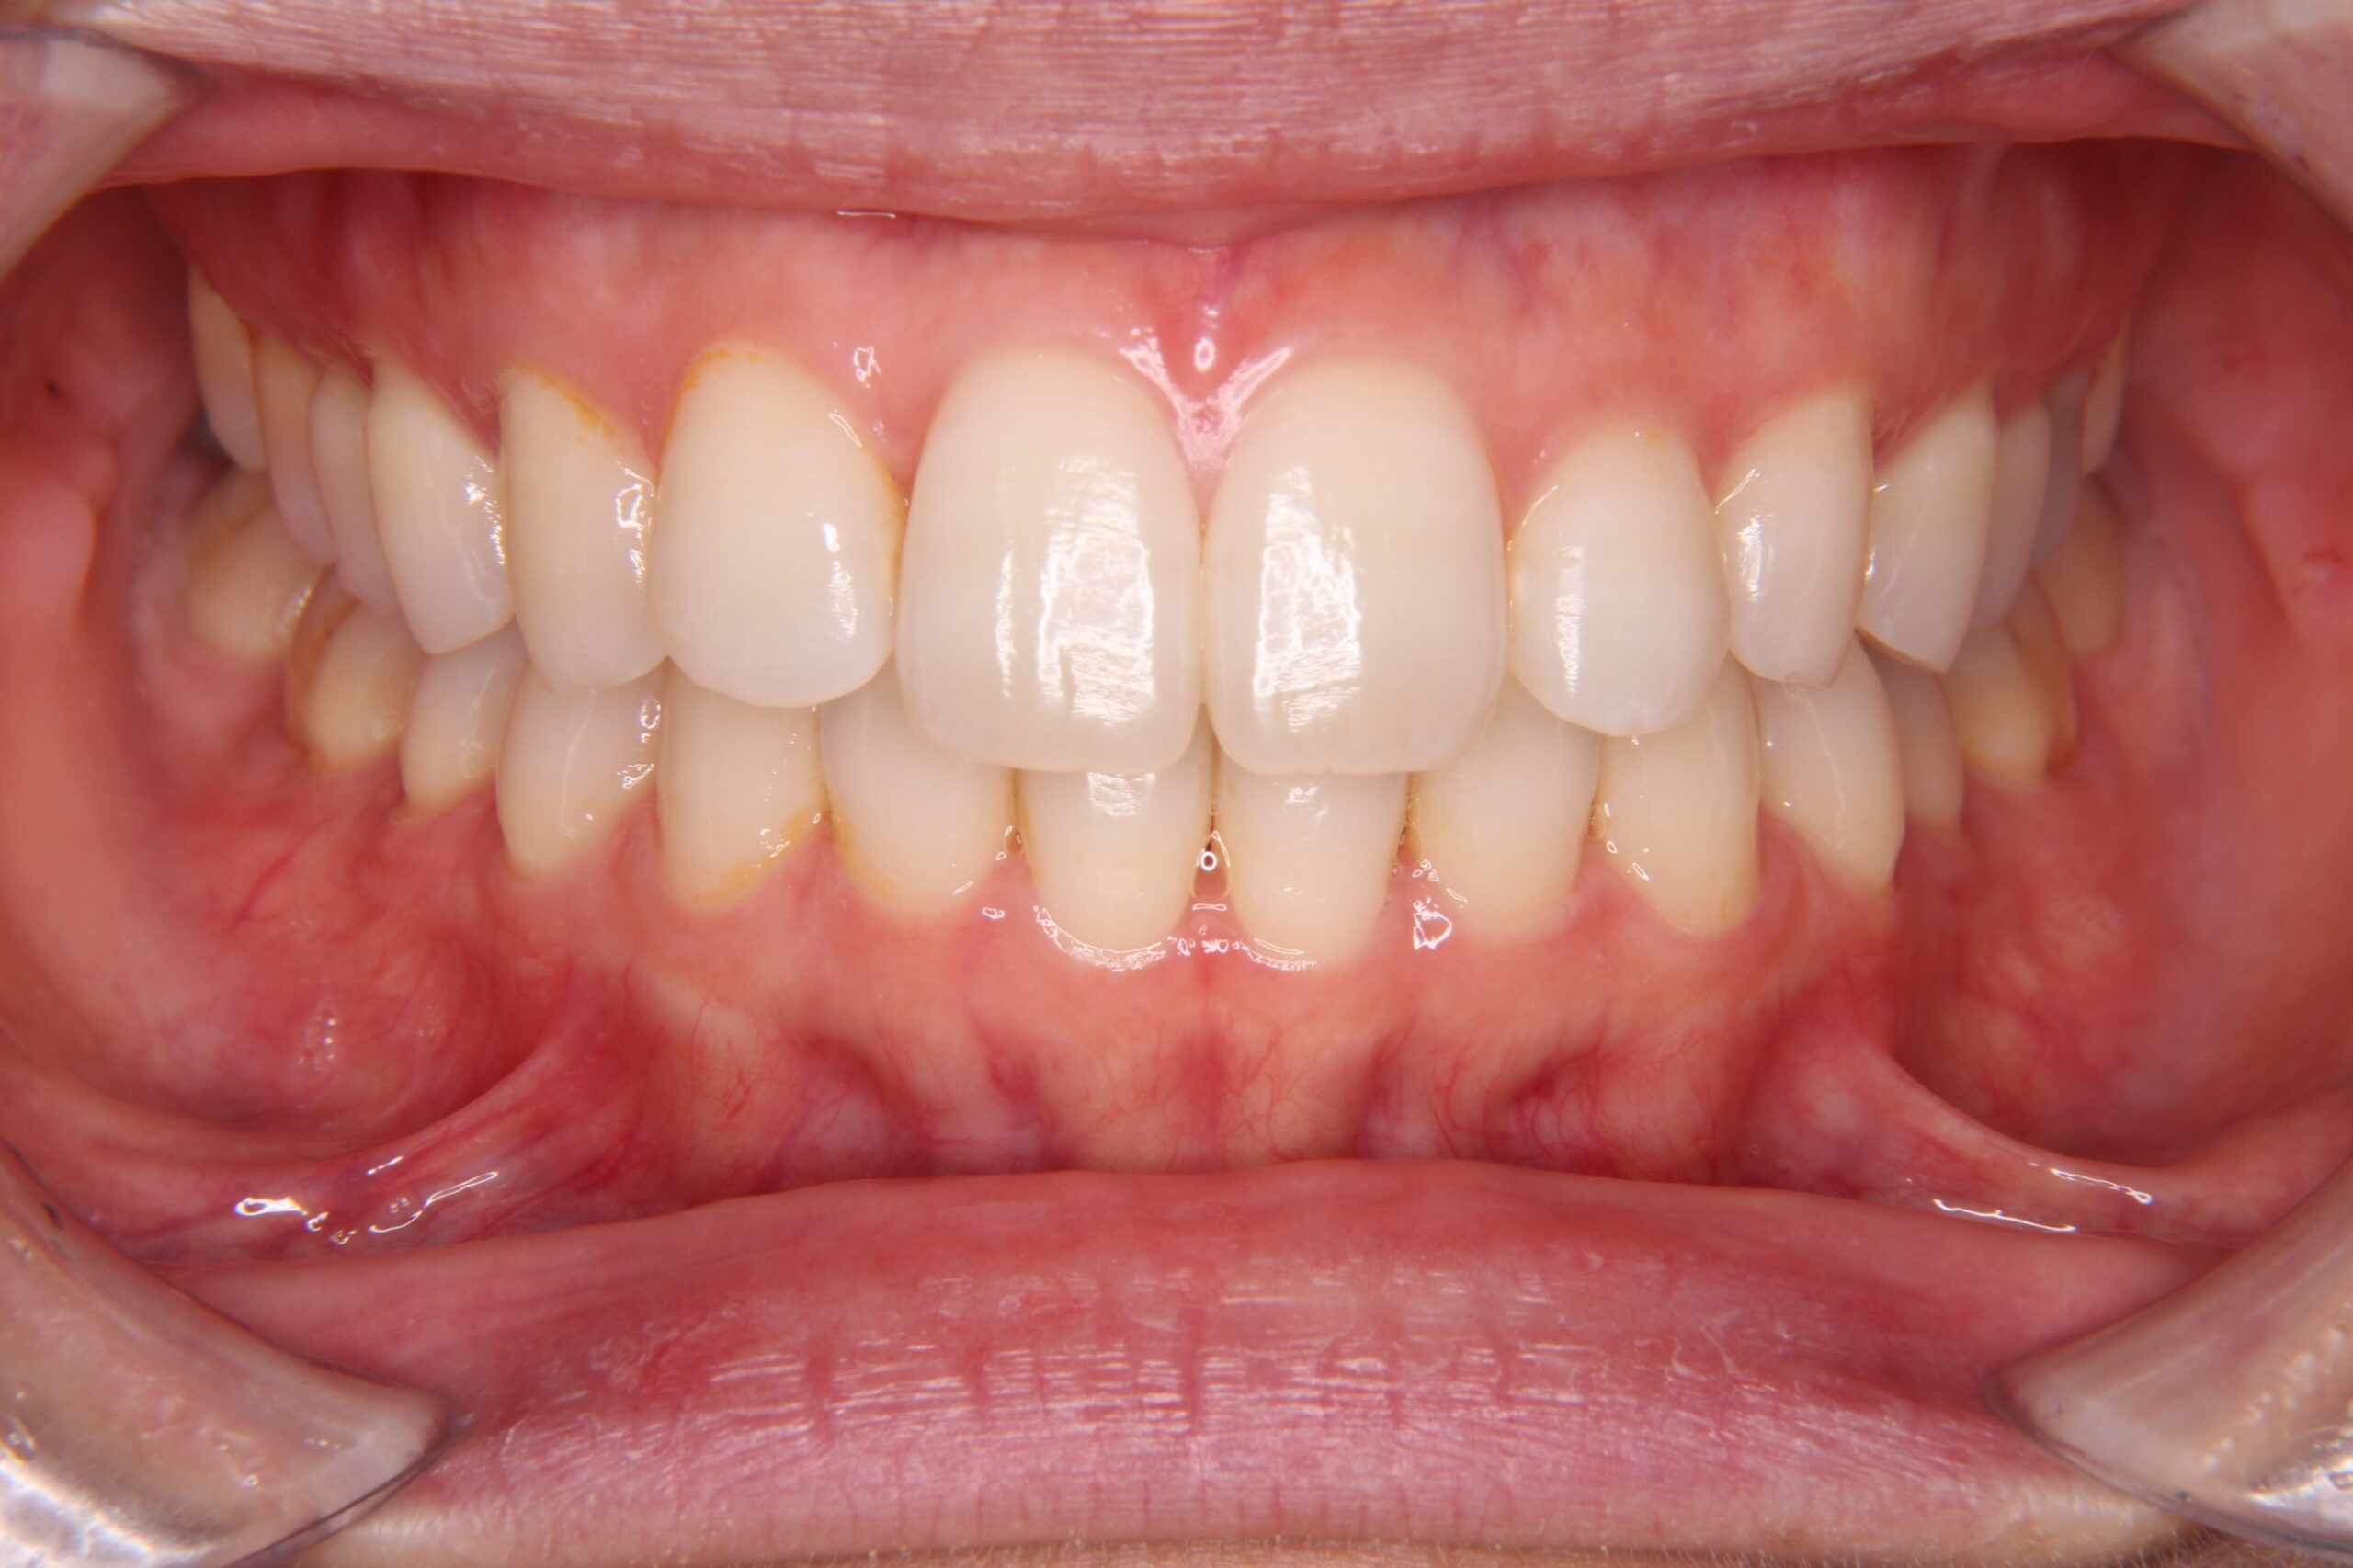

矯正後の歯列

矯正後の歯列がこちらです↓↓↓

私自身、矯正でコンプレックスだった歯並びの改善ができて、本当に良かったと思っています!